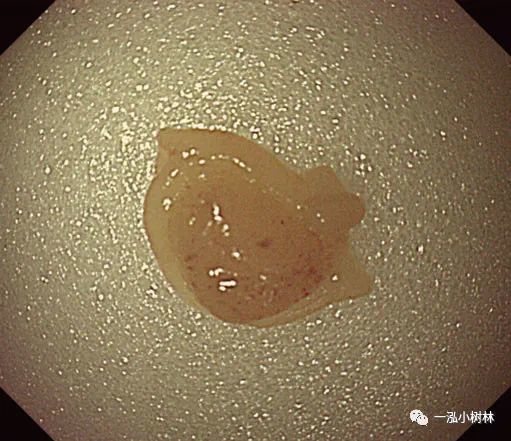

图4f 切除标本保留在息肉切除部位

图4 g息肉摘除术后创面

3.将息肉边缘正常黏膜包括在内,用圈套器夹住并机械横切。切取的速度要快,因为慢的横切会造成黏膜下组织大量的损伤和随后不必要的出血。

4.下一个重要步骤是将息肉切除部位的标本通过结肠镜钳道吸入。切除息肉后,应将结肠镜头指向切除部位,随后吸引。